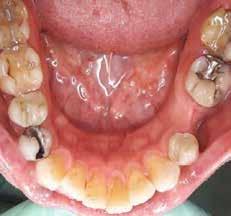

1. ábra: A műtét előtti szituáció, megfigyelhető az implantátumok közötti konkáv terület, ahova könnyen beragad az ételmaradék, és könnyen kialakul a periimplantitis.

Egy 47 éves páciens jelentkezett nálunk egy alsó, hátsó foghiánnyal, ahol jelentős csontfelszívódást tapasztaltunk a moláris fogak korábbi eltávolítása miatt (1. ábra). Két implantátum körül is volt ínyrecesszió, illetve a keratinizált íny mennyisége minimális volt (kevesebb, mint 1 mm). 4 hónappal az implantációt követően ínykorrekciót végeztünk.

2–5. ábra: A metszések és a deepitelizáció. – 6–9. ábra: Félvastag lebeny. – 10. ábra: A nyelezett ínylebeny „bepróbálása”.

horizontális metszéssel kötöttük össze (2–5. ábra). A metszések hosszát és a köztük lévő távolságot minden esetben a lágyszövet augmentációhoz szükséges keratinizált szövet határozza meg. A lebeny deepitelizációját egy 15C-s szikepengével végeztük (6. ábra). Ezt követően félvastag lebenyt preparáltunk (7. ábra). A lebenyt apikálisan, az alapjáról belső, felületes metszéssel felszabadítottuk, hogy passzívan áthelyezhessük és rögzíthessük, feszülés nélkül. Meziális irányba 180 fokkal átforgattuk (8–9. ábra). A meziális papillát alagúttechnikával (tunnelling technique) készítettük elő a graft befogadására (10. ábra). Az így kialakított lebenyt a recipiens ágyban rögzítettük az újonnan kialakított vesztibulum alapjánál 5-0 nem felszívódó PTFE (Coreflon, IMPLACORE) varratokkal. A graftot behajtottuk az ínyszél alá és meziális oldalon rögzítettük PTFE varratokkal (11–14. ábra)

A műtétet követően napi kétszeri, 0,12%-os klórhexidin tartalmú szájvízzel történő öblögetést javasoltunk a páciensnek, két héten keresztül. Gyulladáscsökkentésre 8 óránként 400 mg Ibuprofént javasoltunk, három napon keresztül. A páciens elmondása szerint sem fájdalmat, sem különösebb diszkomfortot nem tapasztalt. Ezt követően, további 4 héten keresztül, 0,2%-os klórhexidin tartalmú szájvízzel történő öblögetést javasoltunk a betegnek és instruáltuk, hogy lehetőleg ne mossa fogkefével az érintett területet. A varratokat egy héttel később távolítottuk el. A donor és a recipiens terület – 10 nappal a műtétet követően – kiválóan gyógyult (15–16. ábra). Az ezt követő kontrollokat a következő időpontokban ejtettük meg: kettő, illetve négy héttel a műtét után, majd három, hat és tizenkét hónappal később, ezt követően pedig félévente (17–20. ábra). Minden kontroll alkalmával professzionális fenntartó kezelést végeztünk a területen.